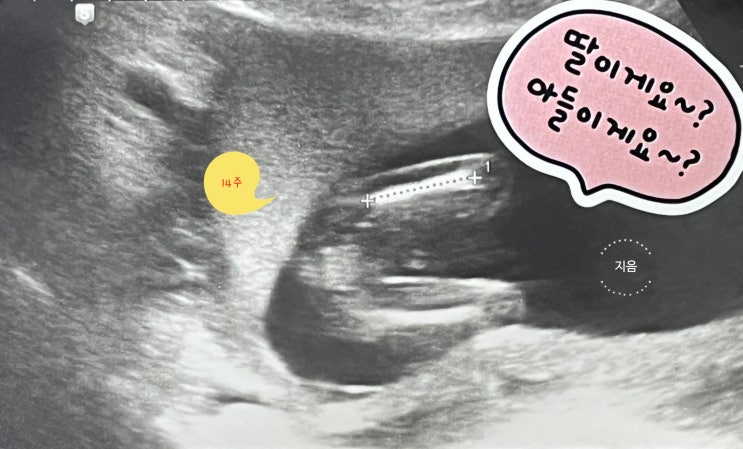

[임신일기] 13~16주 성별 확인, 2차 신경관 결손 검사 결과

임신 10주 분당서울대병원 전원 임신 12주 임당 검사 (119 통과) NT초음파 (콧대, 목덜미 투명대 1.34mm ...